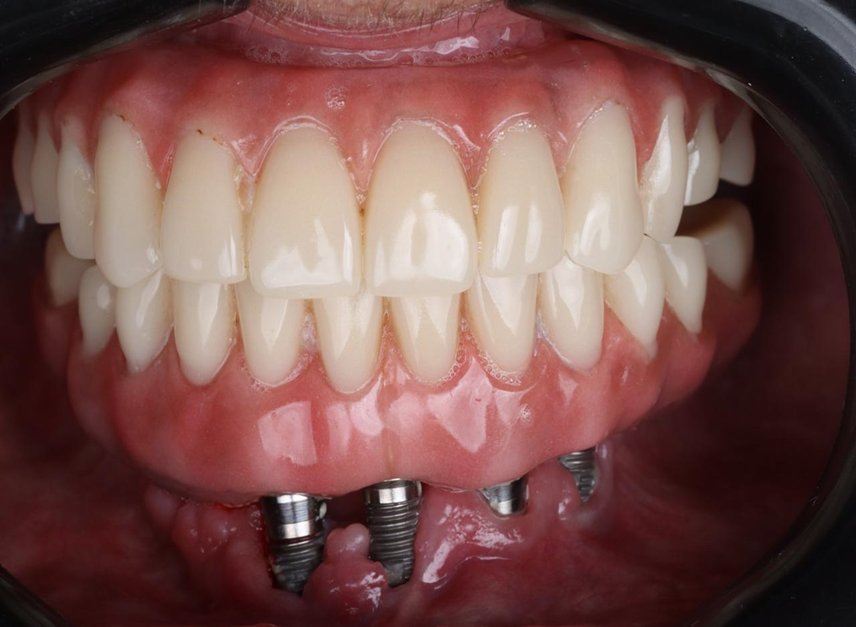

Paciente de 62 anos, do sexo feminino, sem comorbidades e história médica pregressa, apresentava severa reabsorção óssea em regiões anteriores e posteriores da mandíbula devido a uma peri-implantite (Figuras 1A e 1B). Feita a remoção dos implantes, a paciente optou por utilizar uma prótese total mucossuportada até a nova intervenção com prótese do tipo protocolo inferior. Após seis meses, a mandíbula encontrava-se cicatrizada (Figura 2). Como parte do protocolo diagnóstico, foi realizada tomografia computadorizada pela técnica do duplo DICOM. Com a severa perda óssea em região anterior de mandíbula, optamos por realizar a cirurgia de forma guiada, aumentando a previsibilidade e precisão da cirurgia. Os arquivos obtidos foram exportados para o software CoDiagnostiX, possibilitando a realização do planejamento reverso e o subsequente posicionamento virtual dos implantes (Figura 3). Com base no planejamento, optou-se pela instalação de quatro implantes Implacil Osstem CM AR Due Cone (3,5 x 7 mm), associados a mini-cônicos de 1,5 mm (Figuras 4A, 4B, 4C, 4D e 4E). A partir da tomografia da prótese da própria paciente, confeccionaram-se duas guias cirúrgicas: uma guia de pino de fixação (Figura 5) e uma guia de fresagem para a instalação dos implantes (Figura 6). Durante o procedimento cirúrgico, inicialmente foi posicionada a guia de pino de fixação para fresagem dos pinos de fixação e orientação da sequência cirúrgica (Figura 7). Após essa etapa, a guia foi substituída pela guia de fresagem dos implantes (Figura 8), utilizada para a fresagem e inserção dos implantes planejados (Figura 9). Concluída a instalação, optou-se por seguir o fluxo analógico, com a adaptação dos mini-cônicos 1.5 mm (Figura 10), realização da transferência de moldagem com silicona de adição leve e sutura com fio absorvível Vycril 6-0. O guia inicial foi adaptado com broca Maxicut, possibilitando sua utilização como molde de orientação para o laboratório protético (Figura 11). Após a moldagem, foram posicionadas as tampas de proteção sobre os implantes. Na fase protética, transcorridas 48 horas do procedimento cirúrgico, foi realizada a prova clínica da barra metálica e dos dentes (Figura 12). Na etapa subsequente, 72 horas após a cirurgia, procedeu-se à instalação e entrega do protocolo mandibular inferior e radiografia prévia, reabilitando funcional e esteticamente a paciente em curto espaço de tempo (Figuras 13A e 13B).